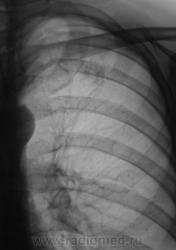

Динамика через 2 месяца после специфического лечения.

Ниже снимки до лечения.

Валентин Львович! Динамика, конечно, слабая. Но "Его Величество" не всегда адекватно реагирует на проводимую терапию. Или это изменения после перенесенного "Его Величества".  Склоняюсь к мысли слабо положительной динамики после проводимой специфической терапии.

Спасибо за высказанное мнение. Мы тоже отметили некоторую положительную динамику.

Считаю, что динамики нет - как был Твс-архив, так и остался...

Пневмосклероз без динамики. Очаговых изменений не видно. Неужели подтвержден туберкулез?

При первичном обследовании туберкулёз подтвержден. Подтвержден и посевом на средах.